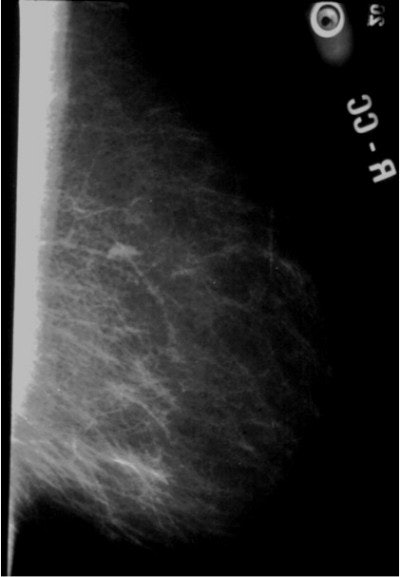

![]() |

| An example of a less-dense glandular pattern more often seen as women reach middle age. Breast cancer is easier to detect against a background of more fatty tissue. Image courtesy of Dr. Michael Linver. |